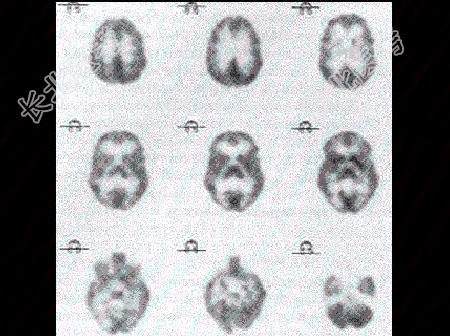

- 女性患者56岁,突发黑朦2h, 无头疼及